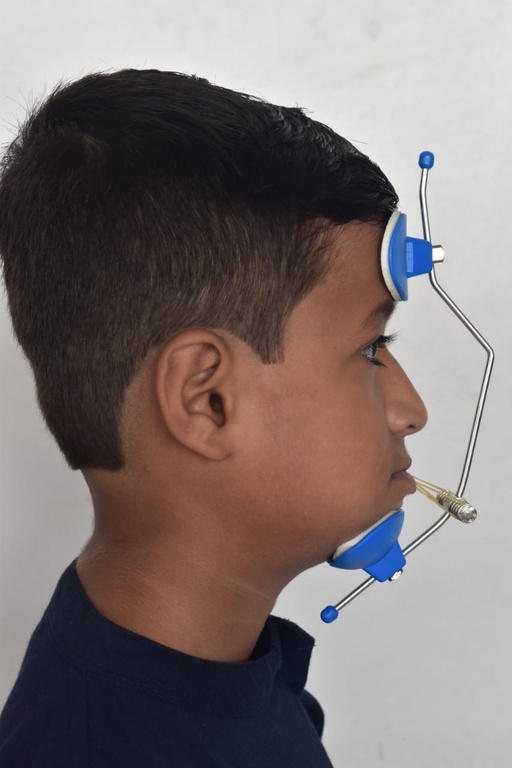

What age is best to start orthodontic treatment?

Orthodontic treatment can be done at any age. However, the best time to start is usually between 9 and 14 years, when most permanent teeth have come in. Adults can also benefit greatly from orthodontic treatment. It’s never too late to get the smile you’ve always wanted!